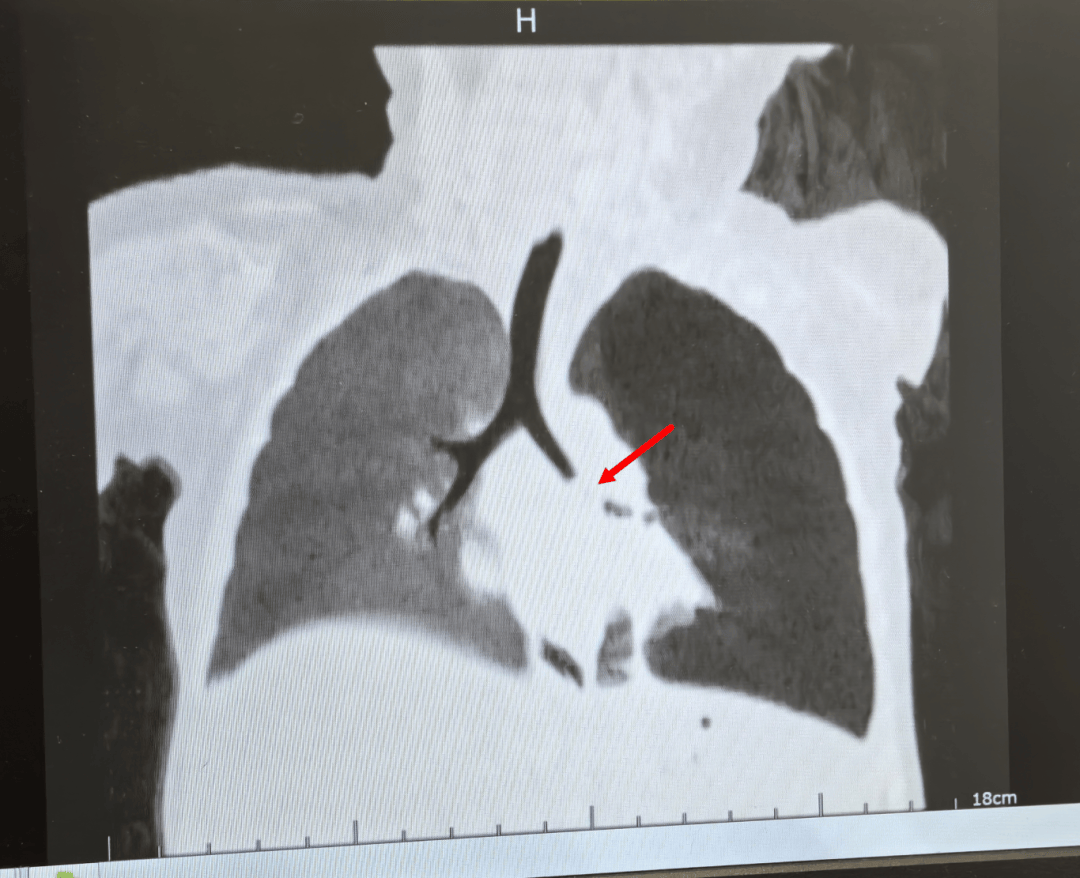

醫生不敢掉以輕心,立即安排肺部CT檢查,結果發現 左肺主支氣管可見巨大的佔位,而且 左肺氣腫得厲害,這次又會是什麼?呼吸內鏡團隊再次「披掛上陣」。氣管鏡下,映入眼帘的竟然是碩大的肉芽樣物,幾乎完全堵塞了氣道,一碰出血,異物卻沒見到。

在經過醫生一番耐心摸索和探查,終於找到了被肉芽遮擋在「身後」的元兇——兩塊碎裂的堅果仁,再次成功完成異物取出。